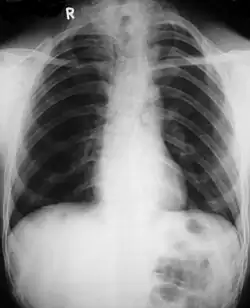

Poor development of the clavicles and a bell-shaped rib cage in a person with CCD